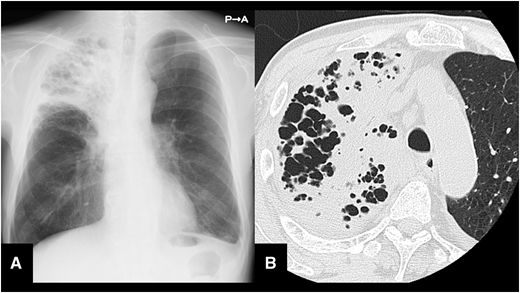

今回は結核に関するClinical PictureがAcceptされました。

タイトルは「Tuberculous pneumonia」です。

「Tuberculous pneumonia」の和訳はそのまま「結核性肺炎」ですが、古くは「乾酪性肺炎」と呼ばれ一般的な肺結核とは異なり突然の高熱、咳嗽を伴い急激な経過を伴います。画像検査では以下に示す通り大葉性肺炎像を呈するため、一見すると重症の細菌性肺炎に見えます。そのためしばしば診断の遅れにつながり公衆衛生上大きな問題になりかねません。

病態としては経気道的に大量の結核菌が散布され、これに対して免疫応答が苛烈に起こることで大葉性肺炎像を呈します。

本症例では結核性肺炎を鑑別疾患として挙げていたため、隔離と迅速な治療開始が達成できました。初期研修医1年目の想い出深い一例です。

抗菌薬に反応しない肺炎を見たときは、悪性腫瘍、耐性菌、真菌、膠原病、好酸球性肺炎を含むアレルギー疾患以外にも「結核性肺炎」を鑑別として忘れないようにしましょう。

掲載雑誌は英国内科学会の発行する内科系雑誌「Quarterly Journal of Medicine(IF 3.1)」です。